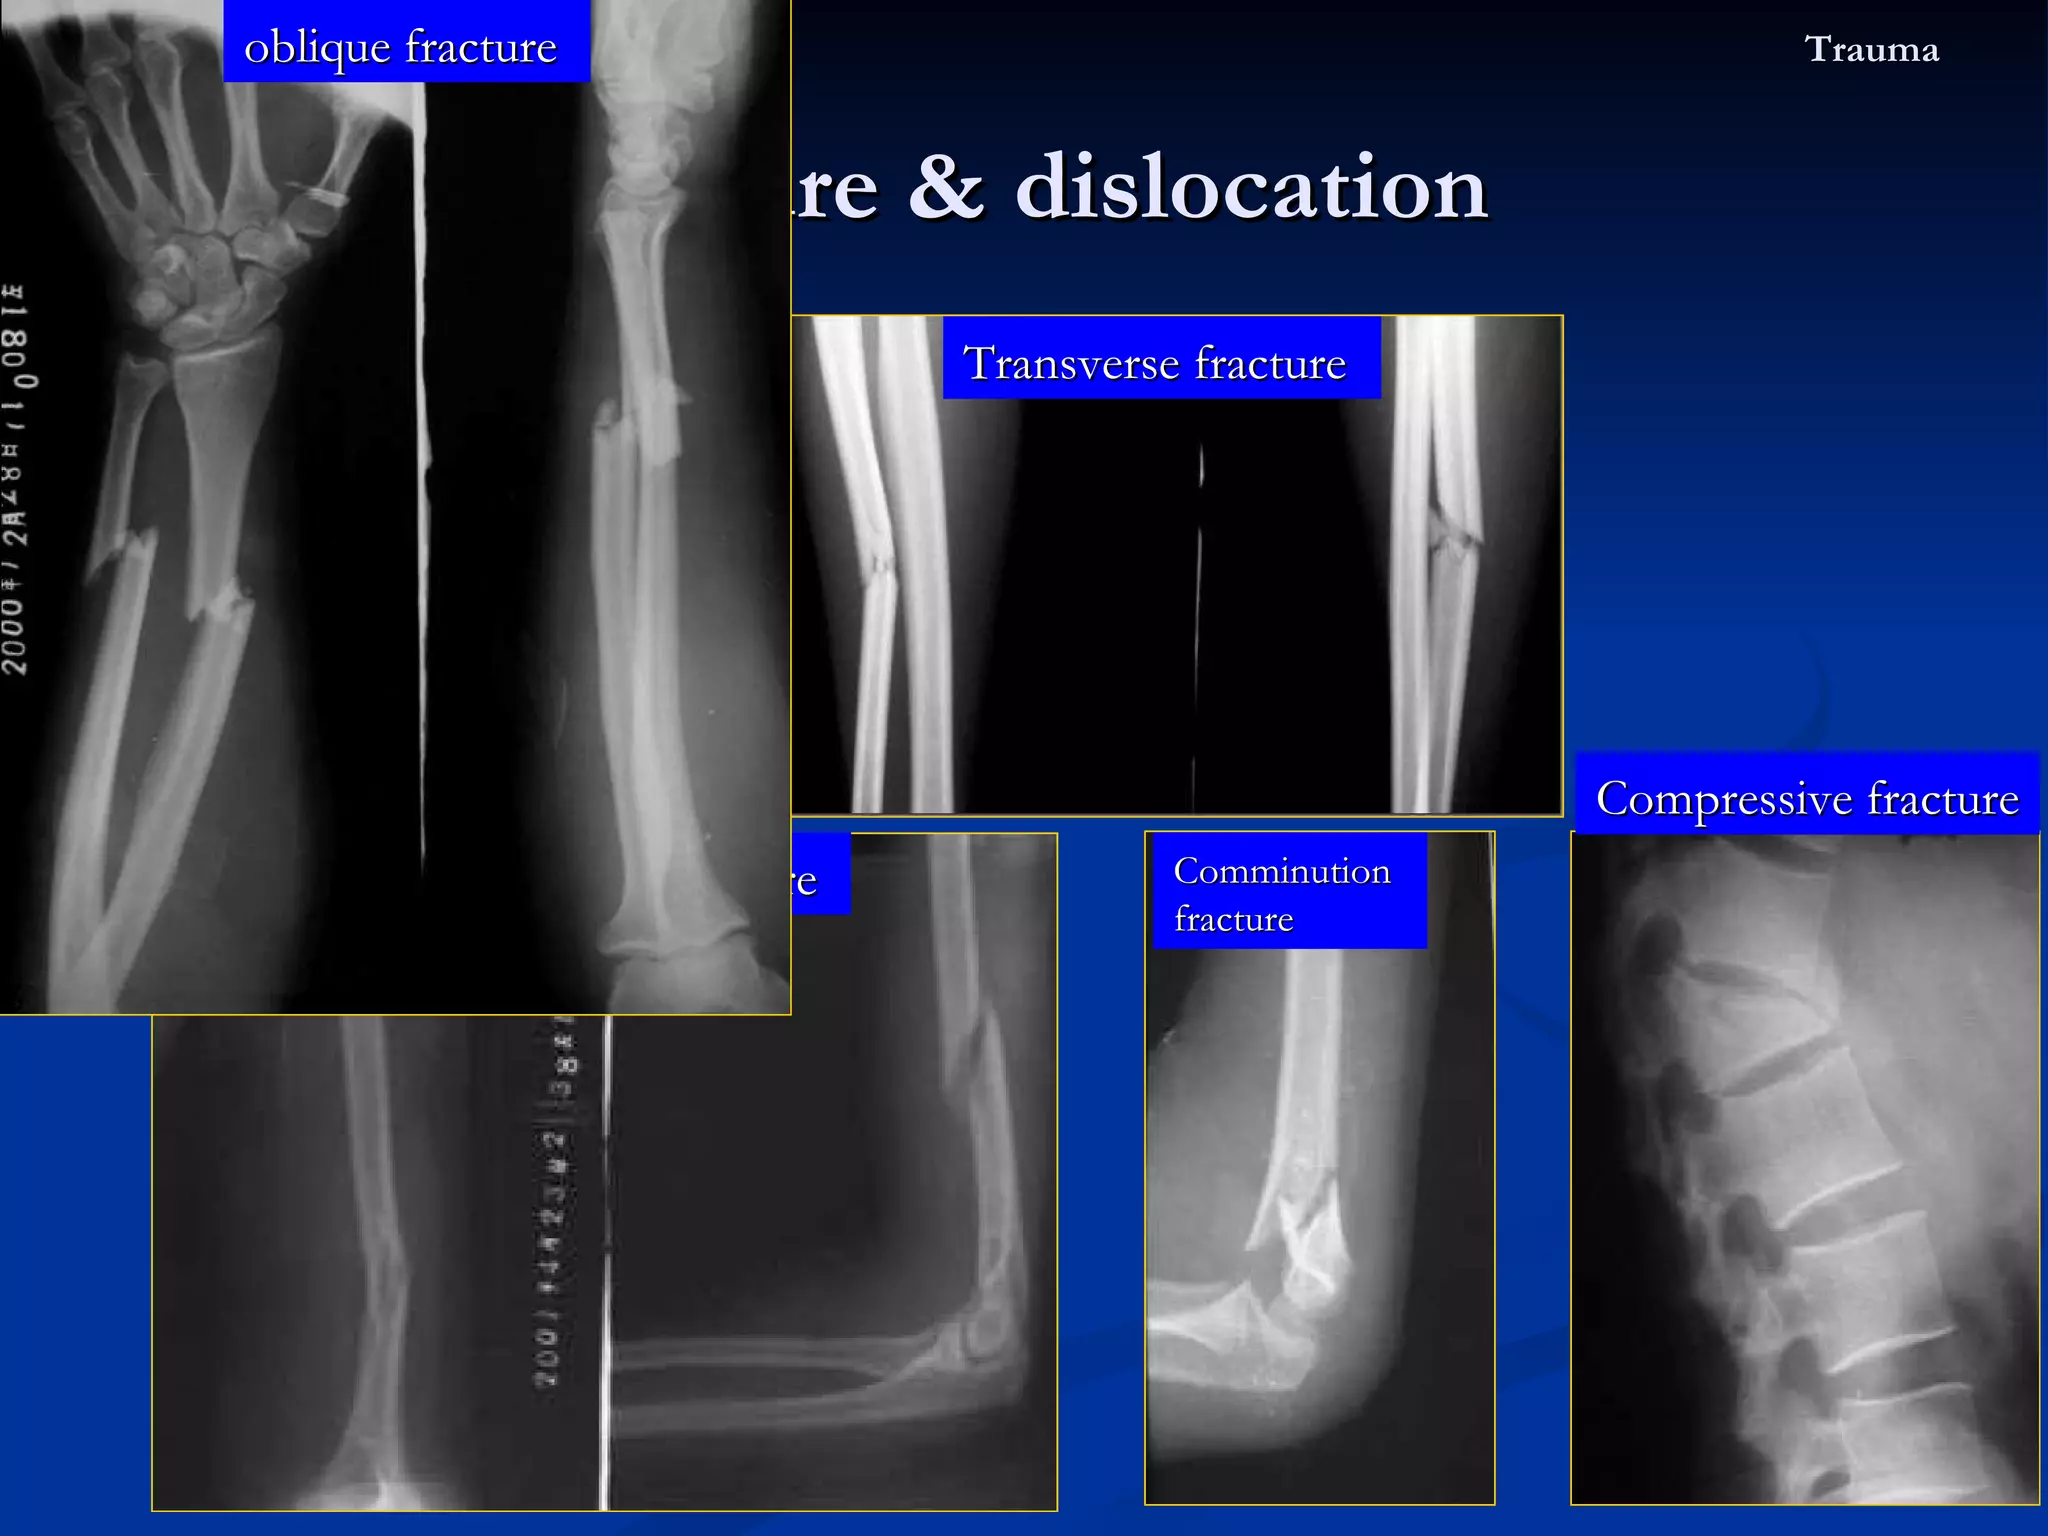

X-ray : Fracture line : the break of bone shows a irregular translucent line (separated  –  translucent overlap - dense) Transverse fracture / oblique fracture / spiral fracture Compression / crush fracture Comminution fracture ( > 2) / segmental fracture Incomplete fracture :  Fracture in children Greenstick fracture :  Epiphyseal separation fracture & dislocation  Trauma

The fracture types Fracture & dislocation  Trauma spiral fracture Transverse fracture Compressive fracture Comminution fracture oblique fracture

X-ray : Fracture line : the break of bone shows a irregular translucent line Transverse fracture / oblique fracture / spiral fracture Comprese fracture Comminution fracture ( > 2) / segmental fracture Incomplete fracture :  Fracture in children Greenstick fracture :  Epiphyseal separation fracture & dislocation  Trauma angling or buckling of the cortex without the lucent fracture line Epiphysis & cartilage plate separated from the metaphysis